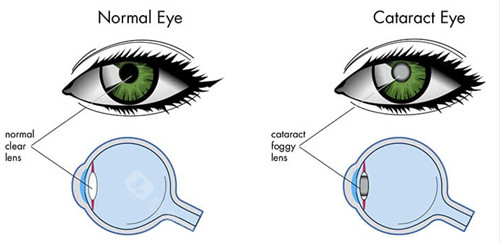

家人们,我做白内障三焦晶体植入手术已经有一段时间啦,现在来给大家好好分享下我1个月和6个月的真实感受,真的就像告别了“毛玻璃”国内外,重见清晰光明!

之前看东西就跟隔着毛玻璃似的,模模糊糊,干啥都不得劲儿。